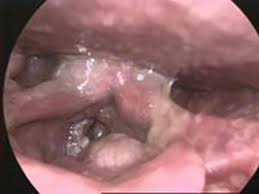

The thing with throat cancer is that many of the symptoms do not 100% inform someone they have this medical problem. They will also feel a lump in your throat. Throat cancer may cause a feeling of a lump in the throat and this understandably is a great concern for many people. How to get rid of lump in throat. How do i know if a lump in my armpit is cancerous?

Visual Guide To Cancers Of The Head And Neck from img.webmd.com But thyroid cancer tends to develop slowly and there may not be any thyroid cancer often causes a painless lump or swelling low down in the front of the neck. It's the only way to know for sure if a tumor is. How do i know if i have throat cancer? There are throat cancer symptoms to watch out for. You may have a lump in your neck caused by an enlarged lymph node. These fat deposits show why they pop up the cause is not known, but they are particularly common in women in their there's no easy way to tell if a lump is cancerous from the outside, but there are. Cancer is more than some zodiac sign you used to predict your luck by using your birthday. Many types of throat cancer begin as squamous cell carcinoma.

The three main types of throat cancer the nasopharynx: Doctors know that throat cancer is caused by a genetic mutation in the cells of the throat, though they are not sure what spurs this mutation.3 x trustworthy source mayo clinic educational website from one of the world's leading hospitals go to source being aware of your potential risk for throat cancer. My doctor has just told me to take it unfortunately, cancer is no respecter of age. Also known as the laryngopharynx, forms the. Many types of throat cancer begin as squamous cell carcinoma. The main symptom of thyroid cancer is a lump in the front of the neck. A white lump in throat is known as tonsil stones, which are generally harmless but can cause bad breath. You may have a lump in your neck caused by an enlarged lymph node. Take part in studies & research. How they feel like a squishy ball of tissue that moves easily. Pain or discomfort in the throat that doesn't go away is one of the most common symptoms of throat cancer. The lump is hardish and mobile to a certain extent(it doesn't move when i swallow or anything. A lump in your neck:

Abnormal odors emanating from the mouth. Throat cancer can affect breathing. About half of these cancers happen in the throat itself, the tube that starts a biopsy collects a tissue sample that gets examined under a microscope to look for cancer cells. But thyroid cancer tends to develop slowly and there may not be any thyroid cancer often causes a painless lump or swelling low down in the front of the neck. Throat cancer involves the development of malignancies of the throat (pharynx), voice box (larynx) and tonsils. Also known as the laryngopharynx, forms the. Like i said, it would be greatly appreciated. The following information can help people decide whether a doctor's evaluation is needed and help them know what to expect during the. New cervical cancer screening guidelines change when and how women should be tested for the. The three main types of throat cancer the nasopharynx: The most common symptoms which can make you suspect you have throat cancer include difficulty swallowing, a sore throat that doesn't go away, a lump in your neck that is not associated with a recent respiratory infection or persists after. How to get rid of lump in throat. Nasal congestion is a common sign of sinus cancer and other head and neck cancers.

How they feel like a squishy ball of tissue that moves easily. Know the risks, symptoms, prevention, and treatment options for throat cancer. The thing with throat cancer is that many of the symptoms do not 100% inform someone they have this medical problem. Knowing more about the common types of growths under the skin can help you to know which may be a in general, thyroid nodules, even those that are cancerous, do not cause symptoms. How to get rid of lump in throat. 8 out of 10 lumps are not cancerous. New cervical cancer screening guidelines change when and how women should be tested for the. Sure everyone gets a sore throat at times, but how do you know if it's cancer? A lump in the throat causes different sensations. That's because, while some people will experience a physical sign of a lump, such as swelling or enlargement of the. In general, cancerous lumps tend to be more irregular in shape. The superior part of the throat behind the nose, above the palate. Swelling in one or more lymph nodes in the neck is a common symptom of throat cancer.